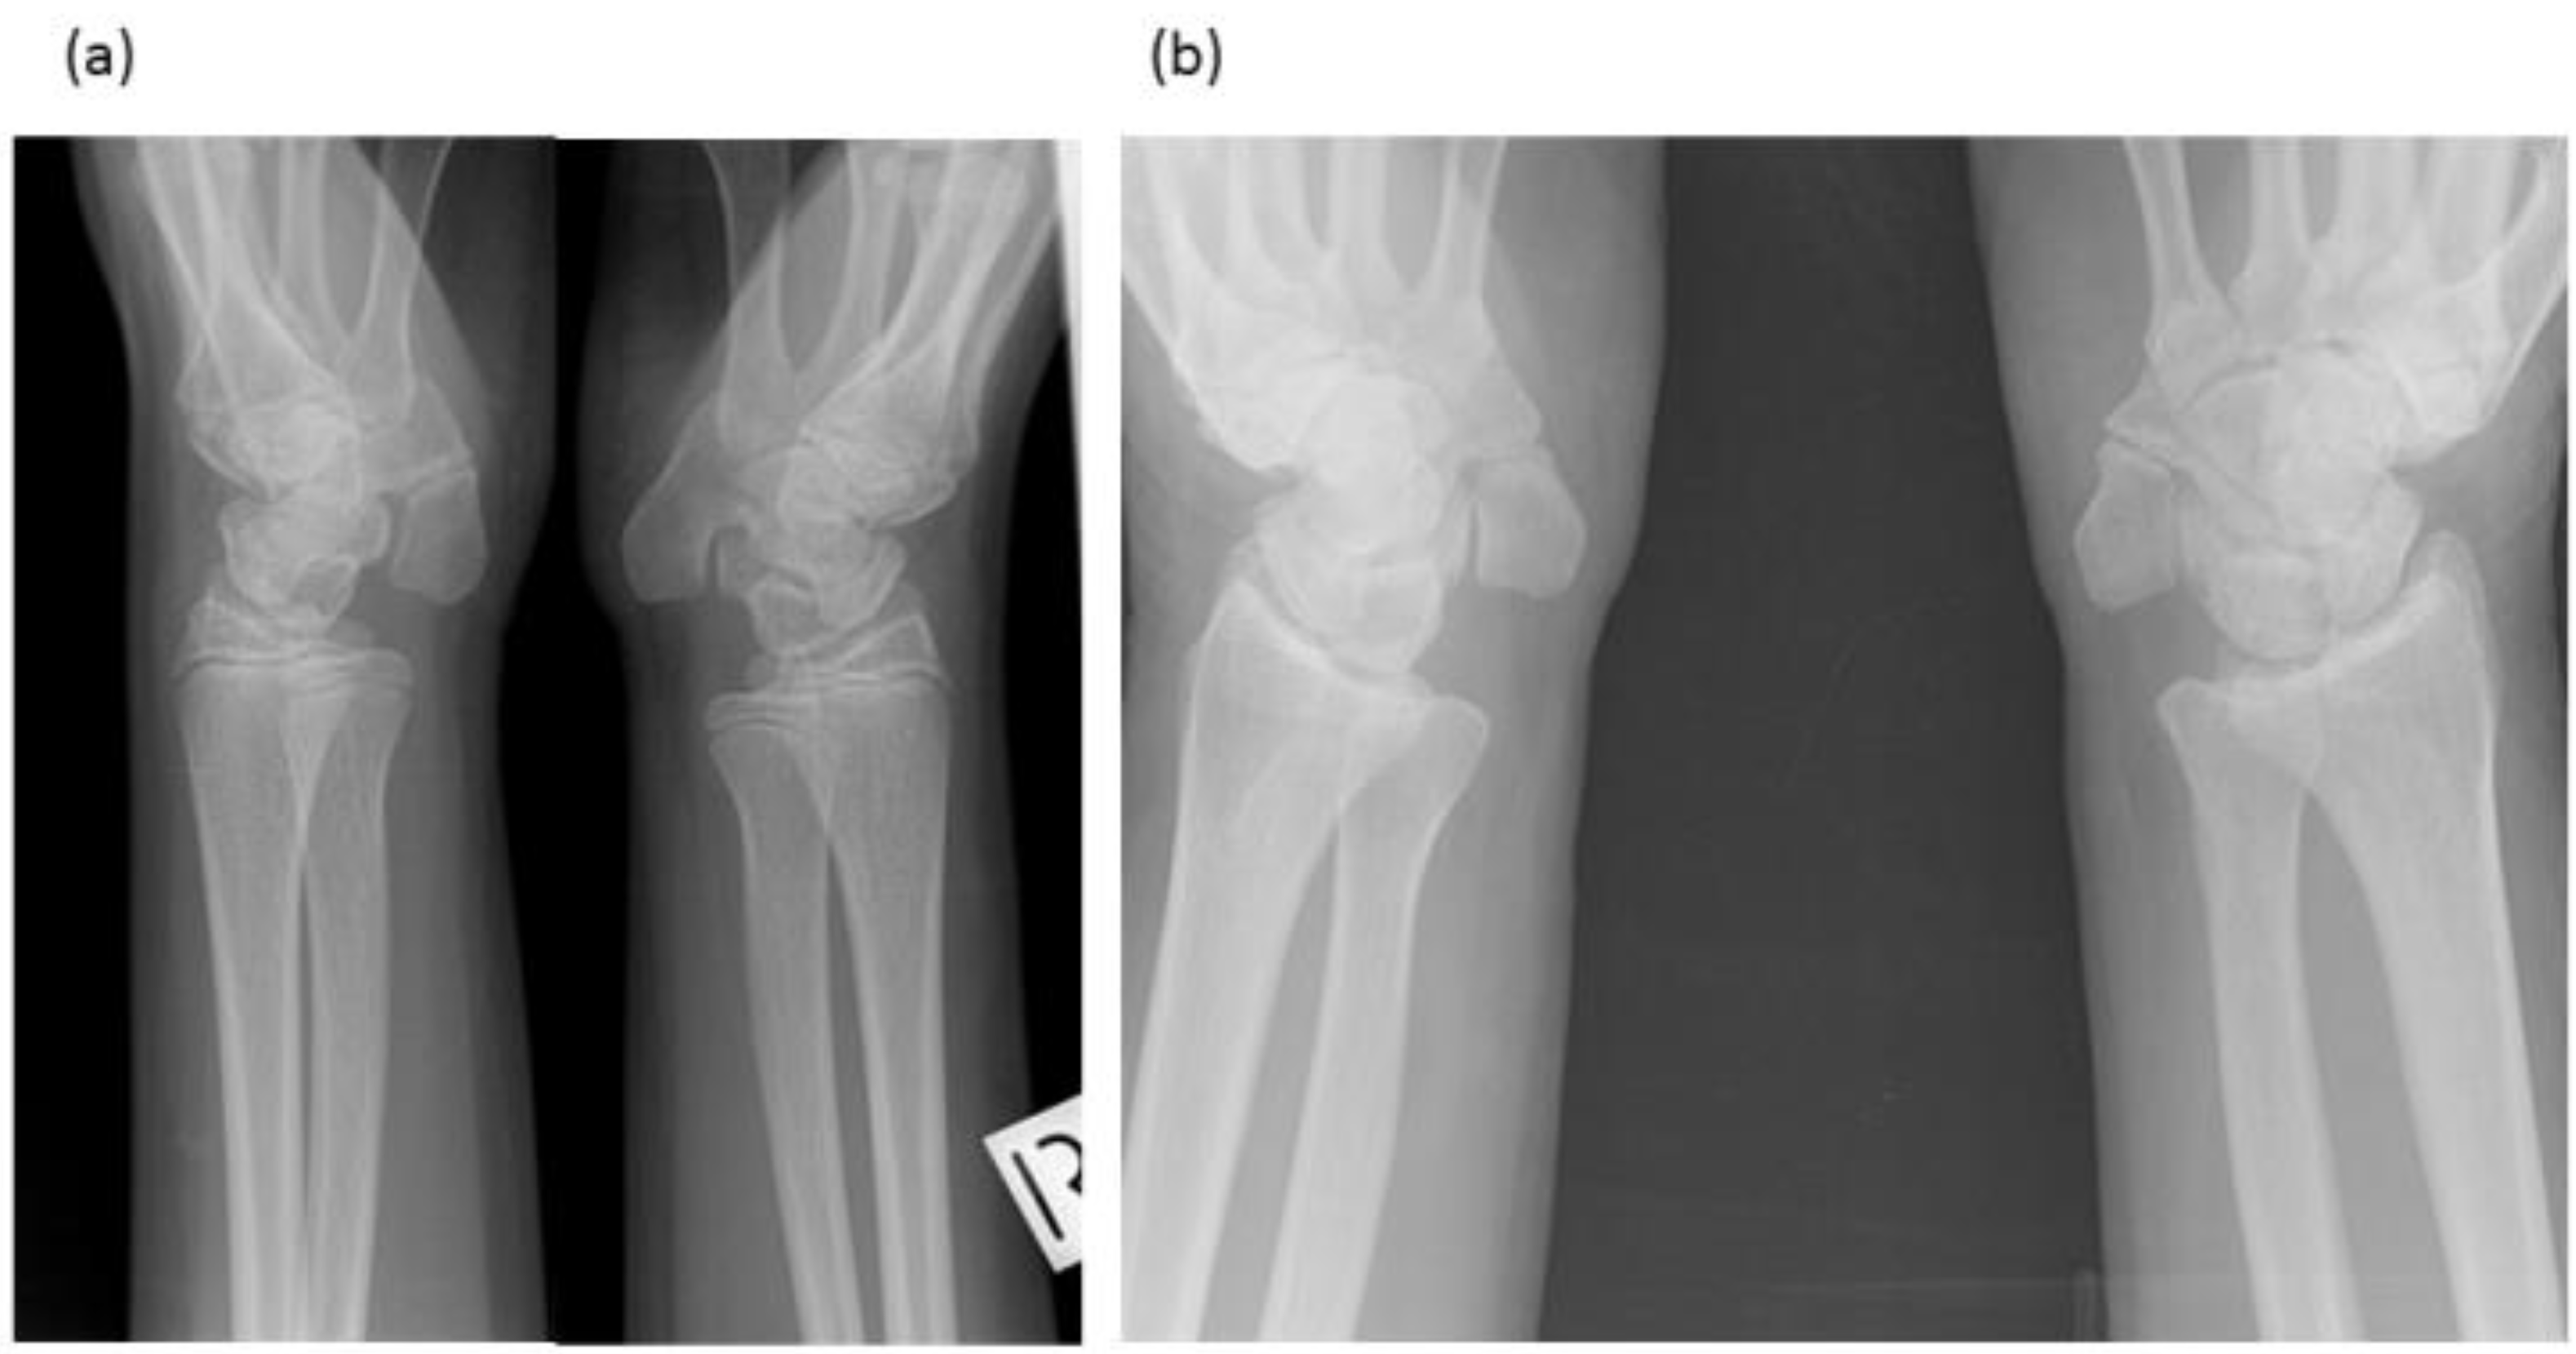

3.1.2. Brother (IV-10)

3.1.3. Brother (IV-9)

| Brother (IV-10) | M | 7–26 | Carpal Tarsal Coalition, Pisiform elongated No hearing impairment or congenital vertebral fusion, Postnatal vertebral fusion, No speech impairment, short tongue and microstomia. |

| Brother (IV-9) | M | 12–19 | Carpal Tarsal Coalition, Pisiform elongated No hearing impairment, Postnatal vertebral fusion, Severe speech impairment, short tongue and microstomia. |